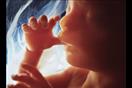

يزن الطفل حوالي 10 أونصات، ويبلغ طوله أكثر بقليل من 6 بوصات، وخلال تلك المرحلة، يعلو الرحم إلى مستوى السرة، ويمكن للطفل أن يمص إبهامه، ويتثاءب، ويتمدد.

وإذا لم تكن الأم قد شعرت بحركة الجنين داخلها في المراحل السابقة، فبنسبة كبيرة ستشعر بها خلال تلك المرحلة.

وعادة ما يتم إجراء فحص الموجات فوق الصوتية لجميع النساء الحوامل في الأسبوع "20"، ومن خلاله يتأكد الطبيب من أن المشيمة سليمة ومتصلة بشكل طبيعي، وأن الطفل ينمو بشكل صحيح، كما يمكن التعرف على نبضات قلب الطفل وحركة جسمه وذراعيه وساقيه، وعادةً ما يمكن معرفة جنس الجنين.